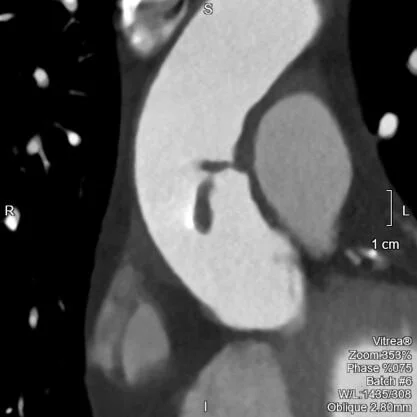

Something new for adrenal nodules

Hiding in plain sight

Lung nodule: Spectral and volumetric.

No-reflow on abdomen CT

A mystifying nodule

The case of the two infarcts

Another mass, another stone

Satisfaction of search

Coital cyst rupture

Anatomy of an old infarct

Roses and islet cells

Urinary stone composition